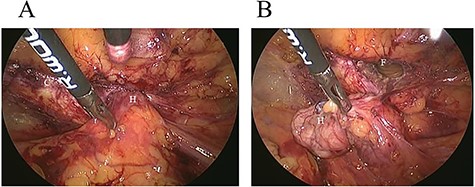

A 62-year-old woman visited our hospital with a 1-day history of lower abdominal pain and bulging from a right groin lesion. Her physical examination showed a right inguinal bulge and pain. Her abdomen was not distended and was without rebound tenderness and muscular defense. However, the bulge in the right groin lesion could not be reduced manually. Contrast-enhanced computed tomography showed a hypodense rounded lesion medial to the right femoral vessels (Fig. 1A) with fluid collection (Fig. 1B), with no intestinal obstruction or ischemia. Based on these physical and radiological findings, the patient was diagnosed as having a right incarcerated femoral hernia containing fat tissue. As there were no clear findings of intestinal obstruction, elective TEP repair was performed 1 day after admission following preoperative evaluation of her general condition. An infra-umbilical incision was made under general anesthesia. The preperitoneal space was created with blunt dissection with the aid of CO2 gas insufflation to a pressure of 12 mmHg. Two 5-mm trocars were inserted into the left mid-abdomen. The hernia sac had herniated into the right femoral canal (Fig. 2A). Therefore, we diagnosed a right incarcerated femoral hernia containing greater omentum. However, there were no findings of abscess formation or small bowel necrosis. We were able to release the hernia sac using laparoscopic forceps (Fig. 2B). After reduction of the hernia sac, 10.3 × 15.7 cm polypropylene mesh was placed in the preperitoneal space and fixed to Cooper’s ligament with a fixation device (ProTack™, COVIDIEN) (Fig. 3). Intraperitoneal observation was not performed because we considered it unnecessary to confirm the presence of intestinal damage. The patient’s postoperative course was uneventful, and she was discharged from our hospital 3 days after surgery. Presently, at 1 month after surgery, the patient is doing well without recurrence or mesh infection.

Intraoperative findings. A: The hernia sac (H) had herniated into the right femoral canal. B: The hernia sac (H) was released from the femoral canal (F) with laparoscopic forceps.